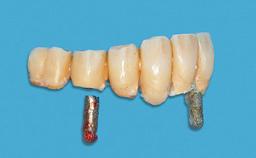

Prosthesis Type RDP

SAC Level Advanced

Defining Characteristics Fully edentulous lower jaw to be rehabilitated with an implant-borne removable overdenture

Loading Protocol Conventional/early